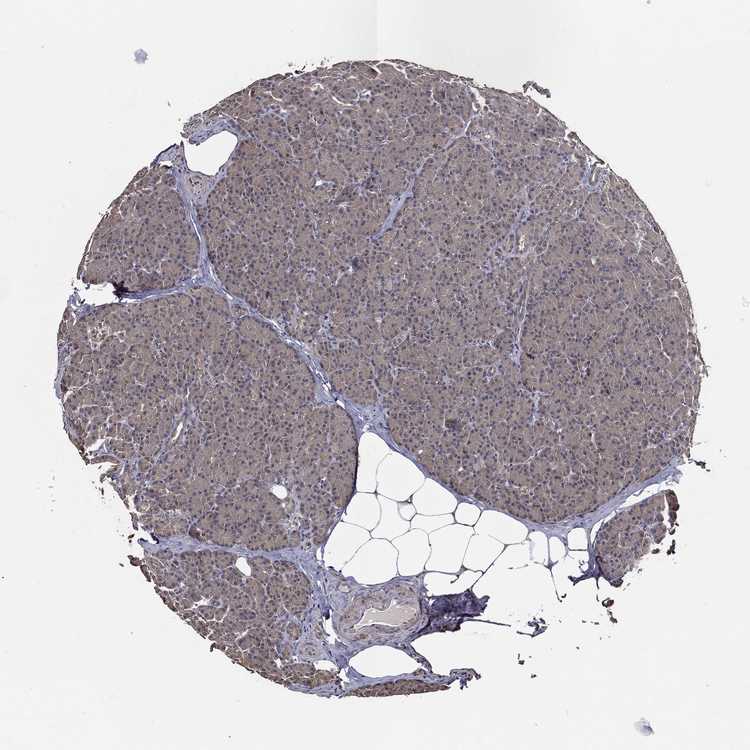

PANCREAS - Antibody stainingi

Antibody staining in the annotated cell types in the current human tissue is reported as not detected, low, medium, or high, based on conventional immunohistochemistry profiling in selected tissues. This score is based on the combination of the staining intensity and fraction of stained cells.

Each image is clickable and will lead to virtual microscopy that enables deeper exploration of all samples and also displays staining intensity scores, fraction scores and subcellular localization as well as patient and tissue information for each sample.

Antibody HPA016820Antibody HPA019887Antibody HPA032101

Exocrine glandular cells MediumMediumNot detected

Pancreatic endocrine cells -MediumNot detected